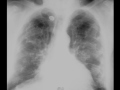

Calcified Pleural Plaques on Chest X-ray

Patient with asbestos related pleural disease. Chest x-ray demonstrates calcified pleural plaques.